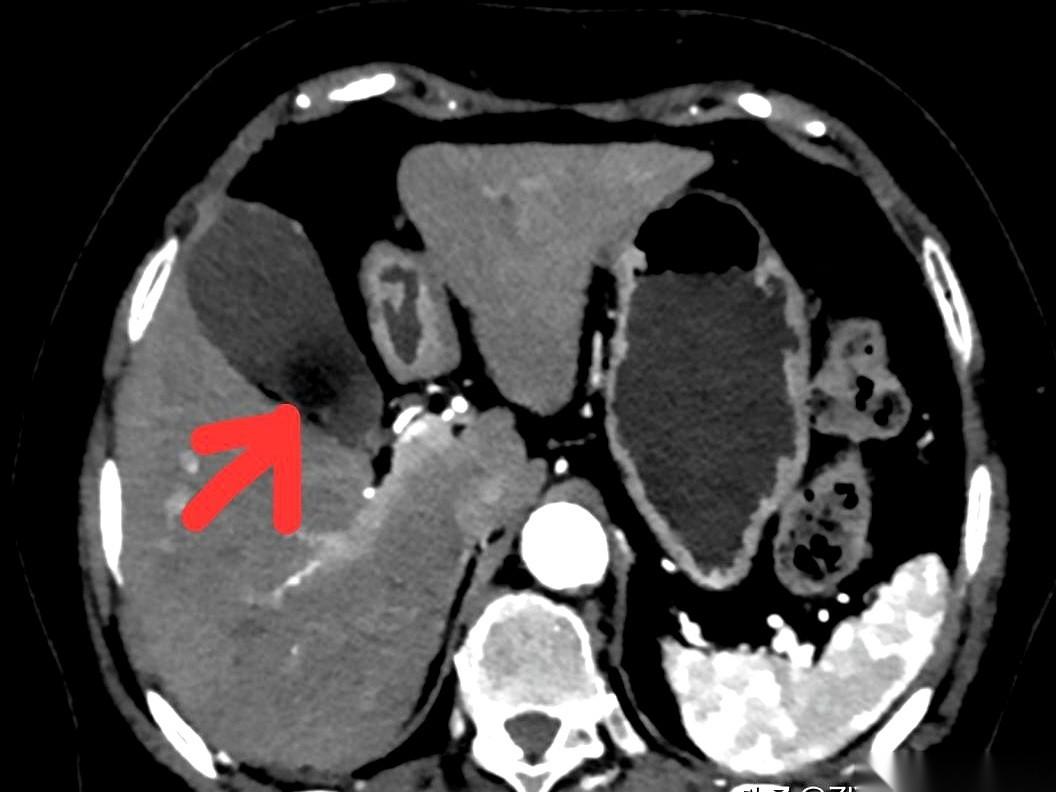

我跟你讲个事儿,绝了。 一个阿姨,肚子疼了20天,跑去做CT,报告白纸黑字写着:胆囊没毛病。 可她就是疼啊!转头又去做了个B超,好家伙,B超上清清楚楚,一堆石头。 同一个胆囊,同一个时间,俩机器,两种命。 这找谁说理去? 后来才知道,石头这玩意儿,也分“三好学生”和“隐形刺客”。 阿姨得的那种,叫胆固醇结石。说白了,就是一肚子“油”结晶了。 这东西密度低,跟胆汁儿差不多。 在普通CT眼里,它俩就是一伙儿的,跟透明的冰块扔进了白开水里一样,根本看不出来。CT报告当然写“没事”。 但B超不一样,它靠的是耳朵,是声波。 石头和液体,在它听来,动静完全不同。一下就给揪出来了。 所以啊,有时候真不是机器骗你。 是你身体里那个“对手”太狡猾。 这事儿给我最大的感触就是,别太迷信一张报告。 尤其是当你的身体还在持续发出警报的时候。 你的疼,你的难受,才是最真实的报告。 机器是死的,人是活的。多问一句,换个法子查,可能就是天壤之别。 千万,千万要信你自己的身体。 它不会骗你。